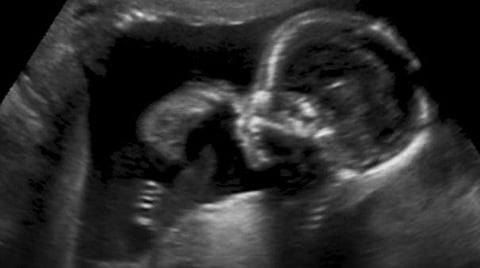

வாஷிங்டன்: அமெரிக்காவில் தாயின் கருவில் இருந்த சிசுவுக்கு மூளையில் அறுவை சிகிச்சை செய்து மருத்துவர்கள் சாதனை புரிந்துள்ளனர்.

மருத்துவ உலகில் நாளும் பல சாதனைகளை மருத்துவர்கள் புரிந்து வருகின்றனர். அந்தவகையில் மற்றுமொரு சாதனை அமெரிக்காவில் நடந்தேறியுள்ளது. அமெரிக்காவை சேர்ந்த பெண் ஒருவர் பாஸ்டனில் உள்ள மருத்துவமனையில் தனது 34 வது வார கர்ப்ப கால பரிசோதனைக்காக சென்றிருக்கிறார். அப்போது வயிற்றில் இருக்கும் அவரது குழந்தைக்கு மூளையிலிருந்து இதயத்திற்கு ரத்தத்தை எடுத்தும் செல்லும் நாளங்கள் வளர்ச்சி அடையாமல் இருந்ததை மருத்துவர்கள் கண்டறிந்தனர்.

இந்த நிலையில் அக்குழந்தைக்கு தாயின் வயிற்றிலே அறுவை சிகிச்சை செய்ய பாஸ்டனில் உள்ள டேரன் ஆர்பாக் தலைமையிலான மருத்துவர்கள் குழு முடிவு செய்தது. இதனைத் தொடர்ந்து வெற்றிக்கரமாக சிசுவுக்கு மருத்துவர்கள் அறுவைச் செய்து முடித்துள்ளனர். அறுவை சிகிச்சைக்கு முடிந்து இரண்டு நாட்களுக்குப் பிறகு அக்குழந்தை பிறந்தது. டென்வர் என்று பெயரிடப்பட்டுள்ள அக்குழந்தை தற்போது நலமாக உள்ளது.